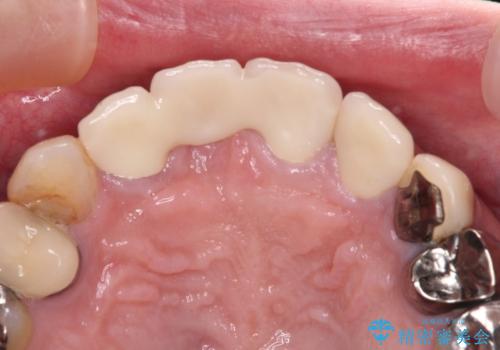

破折している歯は抜歯をし、歯肉が窪んでしまうので、傷口の治りを待って、歯肉移植を行うこととしました。

歯肉移植終了後、オールセラミックブリッジにて補綴することとしました。